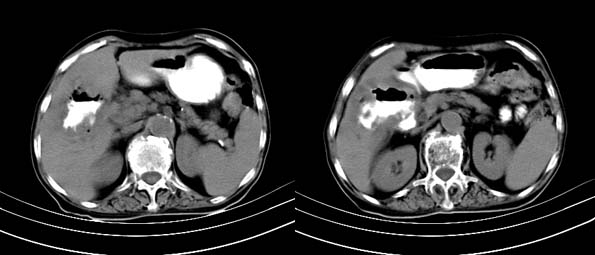

以下是引用bailaode在2008-6-12 22:10:00的发言:[br]资料中未提及患者有无急腹症体征,这个很重要。[br] ct表现:肝内境界模糊之低密度灶,内有含对比剂之液气平面.(提示肝内病灶与胃肠道沟通) [br] 1、根据“长城干红 ”所提供的资料“患者,女,74岁,黑便月余,消瘦,一般状况差,白细胞1万四千”,是否可认为是个慢性病程?那么我首先考虑:十二指肠结核,十二指肠--胆管瘘,继发胆道逆行感染肝脓肿形成。[br] 2、如有急腹症体征则考虑:十二指肠溃疡穿孔?十二指肠占位伴穿孔?

以下是引用拾荒者在2008-6-13 22:13:00的发言:[br]病灶与升结肠、肝脏及十二指肠关系密切,且结肠降段见造影剂影,支持结肠与十二指肠瘘形成,原因及原发病在哪不好定,不过,虽说有风险,但还是应该手术治疗,单纯抗感染估计不行。